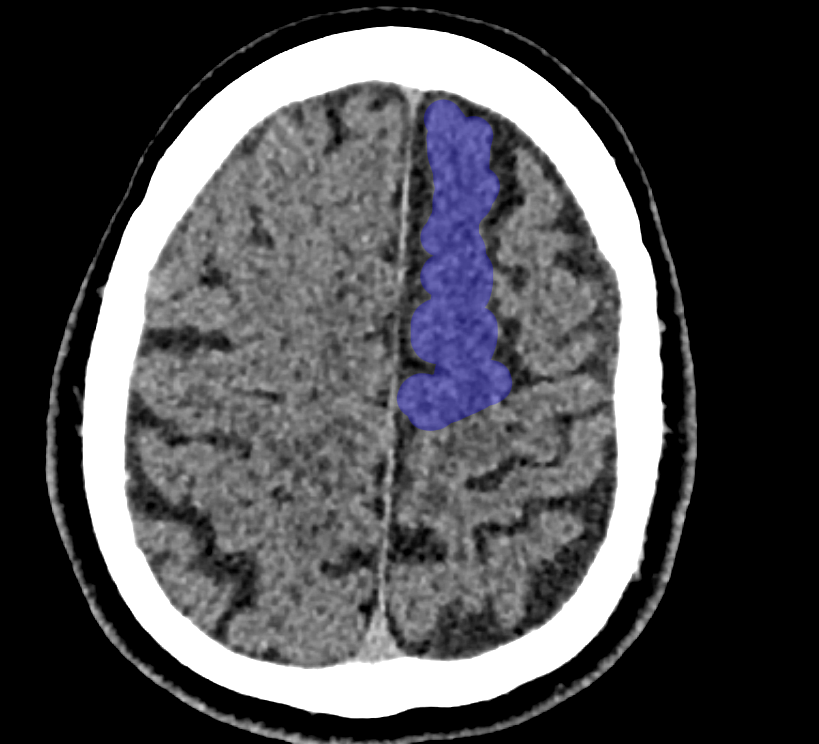

Gyrus frontalis superior CT

Darstellung des Gyrus frontalis superior in einer axialen CT Bildgebung.